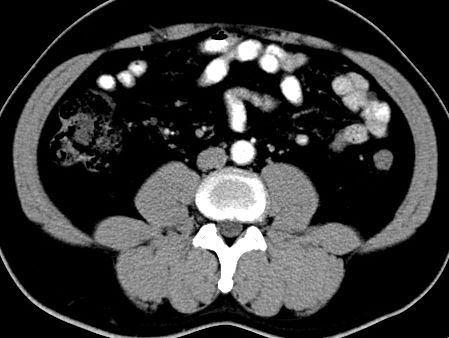

(腹腔)神经鞘瘤

男,48岁,间断性下腹不适1年。

手术探查

:距回盲部28厘米处肠系膜根部可见5*7cm左右包块,质中等硬度,活动度尚可,肝、胆、胰、脾肾未见明显异常。

病理

:(腹腔)

神经鞘瘤

,伴出血、坏死及囊性变,伴淋巴结反应性增生。

免疫组化结果

:sma(-), desmin(-), cd117(-), s-100(+++), nf(-),vimentin(+++).